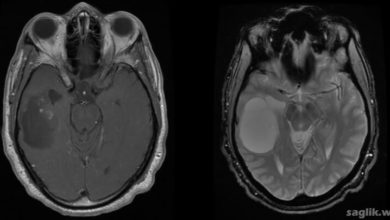

Beyin Metastazı Nedir? Belirtileri, Nedenleri, Tedavisi

Beyin metastazı (brain metastases), vücudun başka bir bölümünde başlayan ve beyne yayılan kanserdir. Beyin metastazı bazen ikincil beyin kanseri veya…